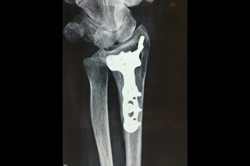

Periprosthetic Fracture THR